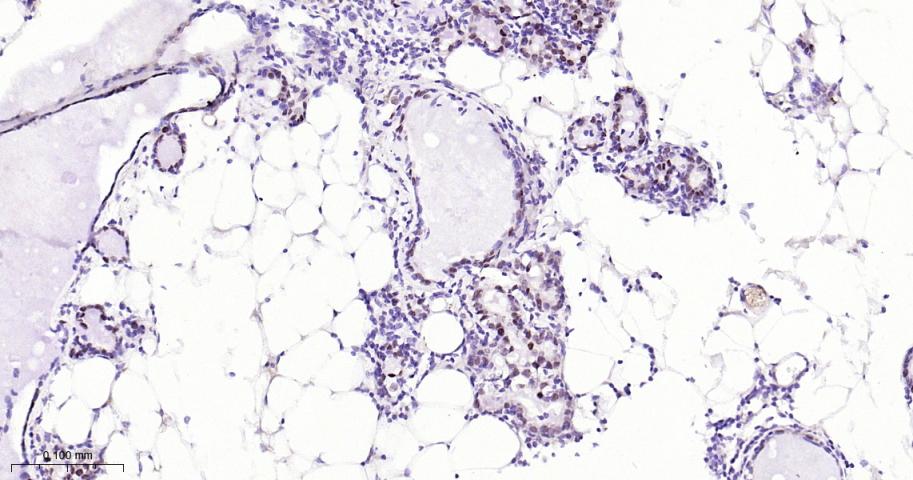

Paraformaldehyde-fixed, paraffin embedded Mouse Breast; Antigen retrieval by boiling in sodium citrate buffer (pH6.0) for 15 min; The section was incubated with AP2 alpha Monoclonal Antibody, Unconjugated (bsm-62206R) at 1:200 overnight at 4°C, followed by conjugation to the bs-0295G-HRP and DAB (C-0010) staining.